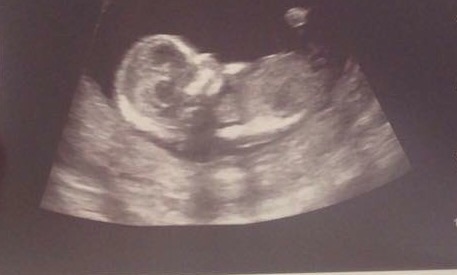

I'm leaning boy, but the pics are small, so it's hard to see the nub properly.

At first glance boy but not sure if what we are seeing above nub is leg - maybe girl?

Thinking boy also if the blip above the nub is part of the nub, do you have any other pics?? :)

Leaning boy too. Would like to see another pic, if you have one. Could be girl. Skull looks girly to me.

That could be a girly nub on that last picture. Could you place a larger version of your first pic? That is where I thought I saw a boy nub.

I think girl, nub looks forked and flat to me

I'm now saying girl. Nub looks girly to me and that skull! Nice and round!

I'm leaning girl!